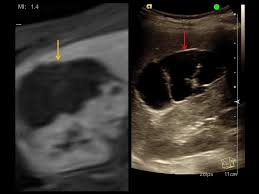

Bildfusion Von Mrt Und Ultraschall Bei Abdominellen Tumoren Healthcare In Europe Com